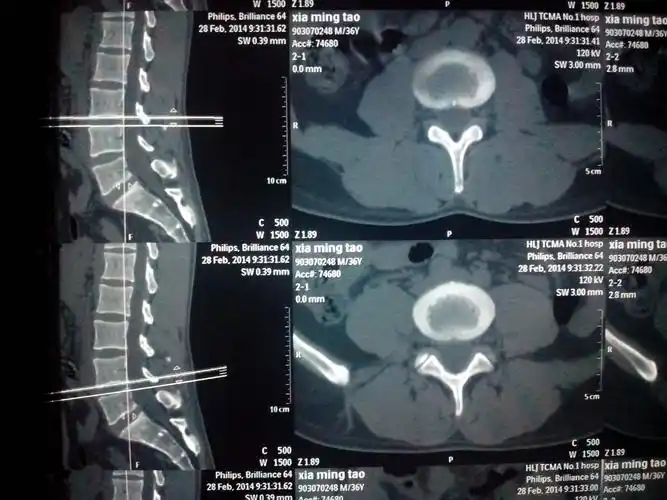

手术技巧凿掉棘突改善胸腰段后凸

ct,x光,核磁共振,谁更适合腰突症检查,你都了解吗?